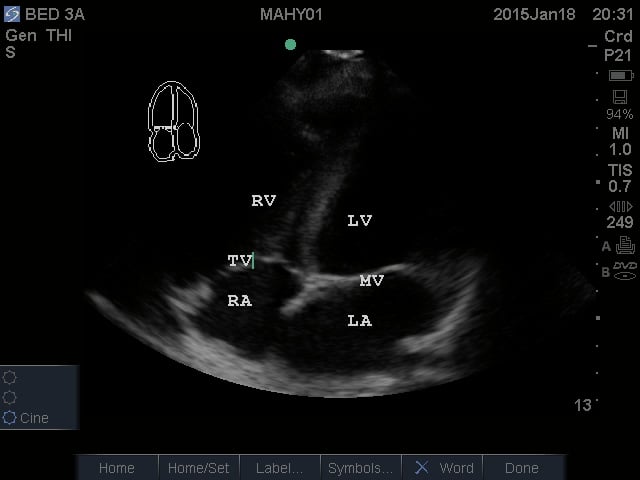

- Apical Four Chamber View: This view shows all four chambers of the heart. The apex is toward the near field with the interventricular septum pointing to approximately the 12 o’clock position. By fanning superiorly, the apical five chamber view can be obtained, with the “fifth chamber” being the LVOT with the aortic valve.

- Figure 4. Apical Four Chamber view. RV = Right ventricle. LV = Left ventricle. TV = Tricuspid valve. RA = Right atrium. LA = Left atrium. MV = Mitral valve